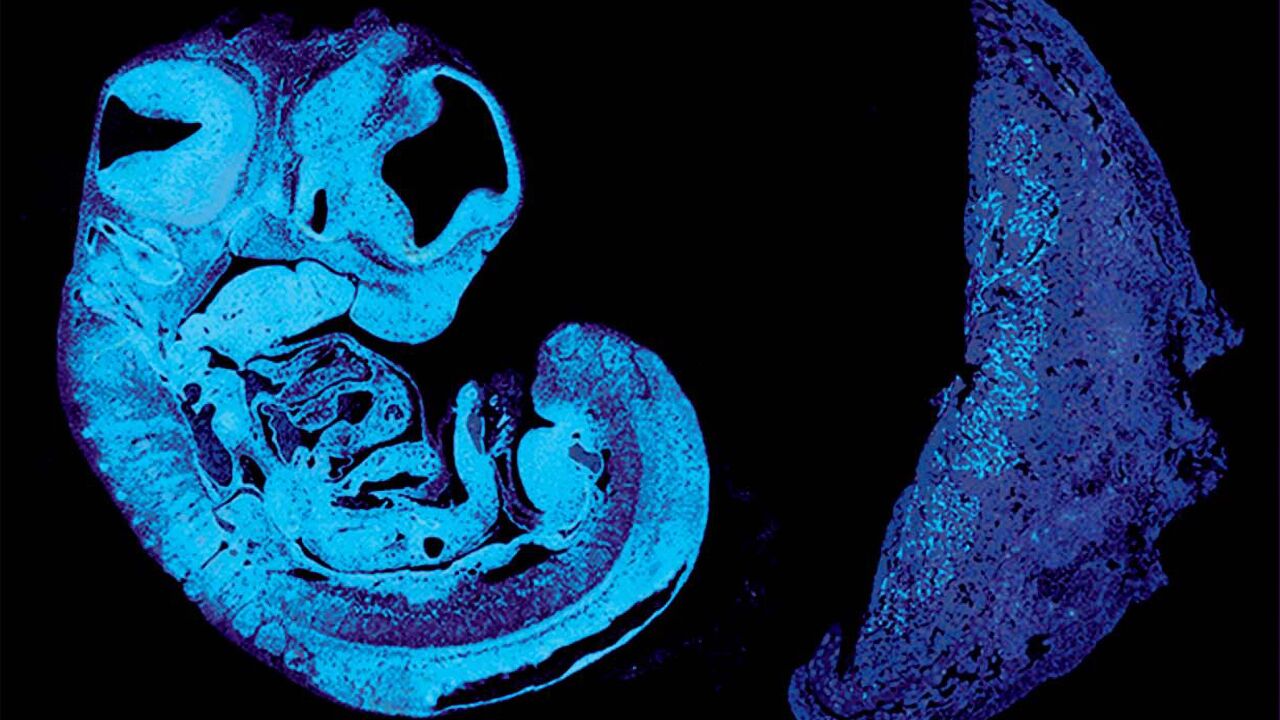

Pràcticament, un 90% dels professionals sanitaris consideren que no estan prou formats per fer front als TEAF, els Trastorns de l’Espectre Alcohòlic Fetal. En aquest sentit, el Departament de Salut alerta que és important conèixer i prevenir aquests trastorns, provocats pel consum d’alcohol durant l’embaràs. Parlem d'una afectació molt prevalent entre els infants adoptats d’Ucraïna i Rússia. Segons un estudi del Departament de Salut, s'ha diagnosticat, aproximadament, en un 50% d’aquests nens. Amb motiu del Dia Mundial de la prevenció del TEAF, la Luisa Maria Conejos, subdirectora general d’addiccions, VIH, infeccions de transmissió sexual i hepatitis víriques de la Secretaria de Salut Pública, explica a 'La Brúixola' les accions que han engegat des del Departament de Salut per prevenir, detectar i millorar l'atenció a les persones i famílies afectades per aquesta problemàtica.